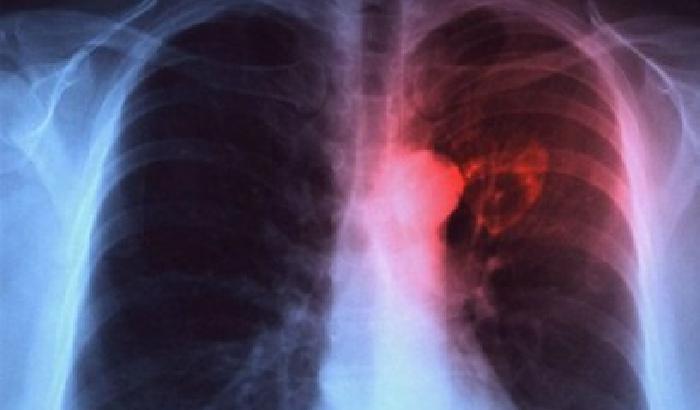

Il tumore del polmone è la prima causa di morte per cancro, responsabile di circa un terzo delle morti per malattie oncologiche. Nonostante gli enormi progressi scientifici, al momento le opzioni terapeutiche sono ancora limitate.

Uno studio su un nuovo farmaco ha dimostrato la possibilità di diminuire la crescita tumorale in studi preclinici condotti in laboratorio sul modello murino con tumore al polmone del sottotipo molecolare K-RAS mutato. La ricerca è frutto di un lavoro internazionale guidato da Elena Levantini dell’Istituto di tecnologie biomediche del Consiglio nazionale delle ricerche (Cnr-Itb) di Pisa dove coordina il Laboratorio di oncologia molecolare, e con incarichi da ricercatrice anche nel reparto di Ematologia/Oncologia dell’ospedale BIDMC della Harvard Medical School di Boston.